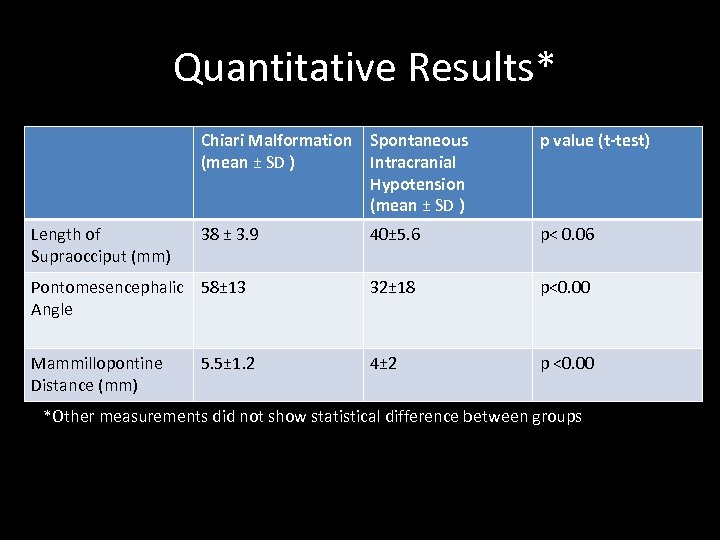

Quantitative Results* Chiari Malformation Spontaneous (mean ± SD ) Intracranial Hypotension (mean ± SD ) p value (t-test) 38 ± 3. 9 40± 5. 6 p< 0. 06 Pontomesencephalic 58± 13 Angle 32± 18 p<0. 00 Mammillopontine Distance (mm) 4± 2 p <0. 00 Length of Supraocciput (mm) 5. 5± 1. 2 *Other measurements did not show statistical difference between groups

Quantitative Results* Chiari Malformation Spontaneous (mean ± SD ) Intracranial Hypotension (mean ± SD ) p value (t-test) 38 ± 3. 9 40± 5. 6 p< 0. 06 Pontomesencephalic 58± 13 Angle 32± 18 p<0. 00 Mammillopontine Distance (mm) 4± 2 p <0. 00 Length of Supraocciput (mm) 5. 5± 1. 2 *Other measurements did not show statistical difference between groups